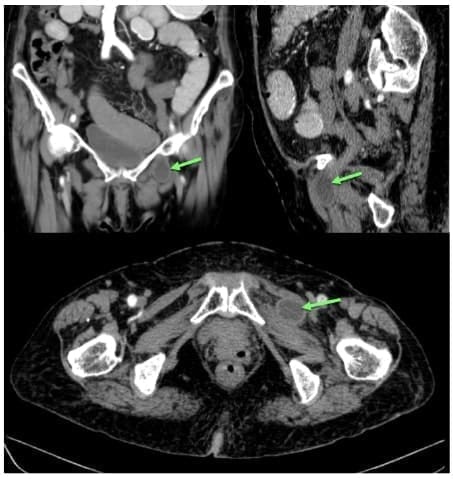

La tomografía computarizada (TC) de pelvis es el estándar dorado para el diagnóstico de esta entidad, porque su sensibilidad puede ser mayor al 90 % 4,25 y es capaz de mostrar hernias bilaterales asintomáticas.

Fue sugerida desde 1983 por Cubillos, y su imagen típica es una burbuja con un nivel hidroaéreo, localizada entre el músculo obturador externo y el pectíneo (Figura 5) o entre ambos músculos obturadores (hernia obturatriz tipo 3 o intermembranosa).

Figura 5. Hernia obturatriz izquierda incarcerada sin signos de isquemia en Tomografía axial computarizada de abdomen doble contraste; muestra el paso del intestino delgado a través del agujero obturador, entre el músculo obturador externo y el pectíneo izquierdo (Flecha verde). Fotografías originales tomadas de los estudios de imágenes de pacientes.

En otras ocasiones, esta imagen representa el segmento de asa intestinal con el saco herniario protruyendo entre los músculos pectíneo y obturador externo en el tipo I 7,10,17,26-28.